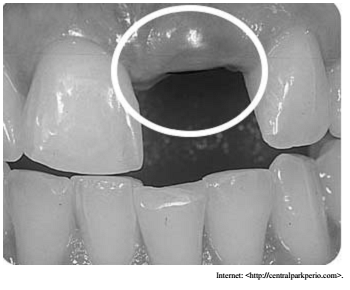

Na imagem precedente, a parte coronal e o parafuso de proteção do implante podem ser vistos por transparência através da gengiva. No que se refere ao controle dessa situação clínica, julgue o item seguinte.

O enxerto subepitelial de tecido conjuntivo apresenta resultados pouco previsíveis quando usado sobre implantes, por não apresentar nutrição adequada para o enxerto, o que aumenta o risco de necrose.